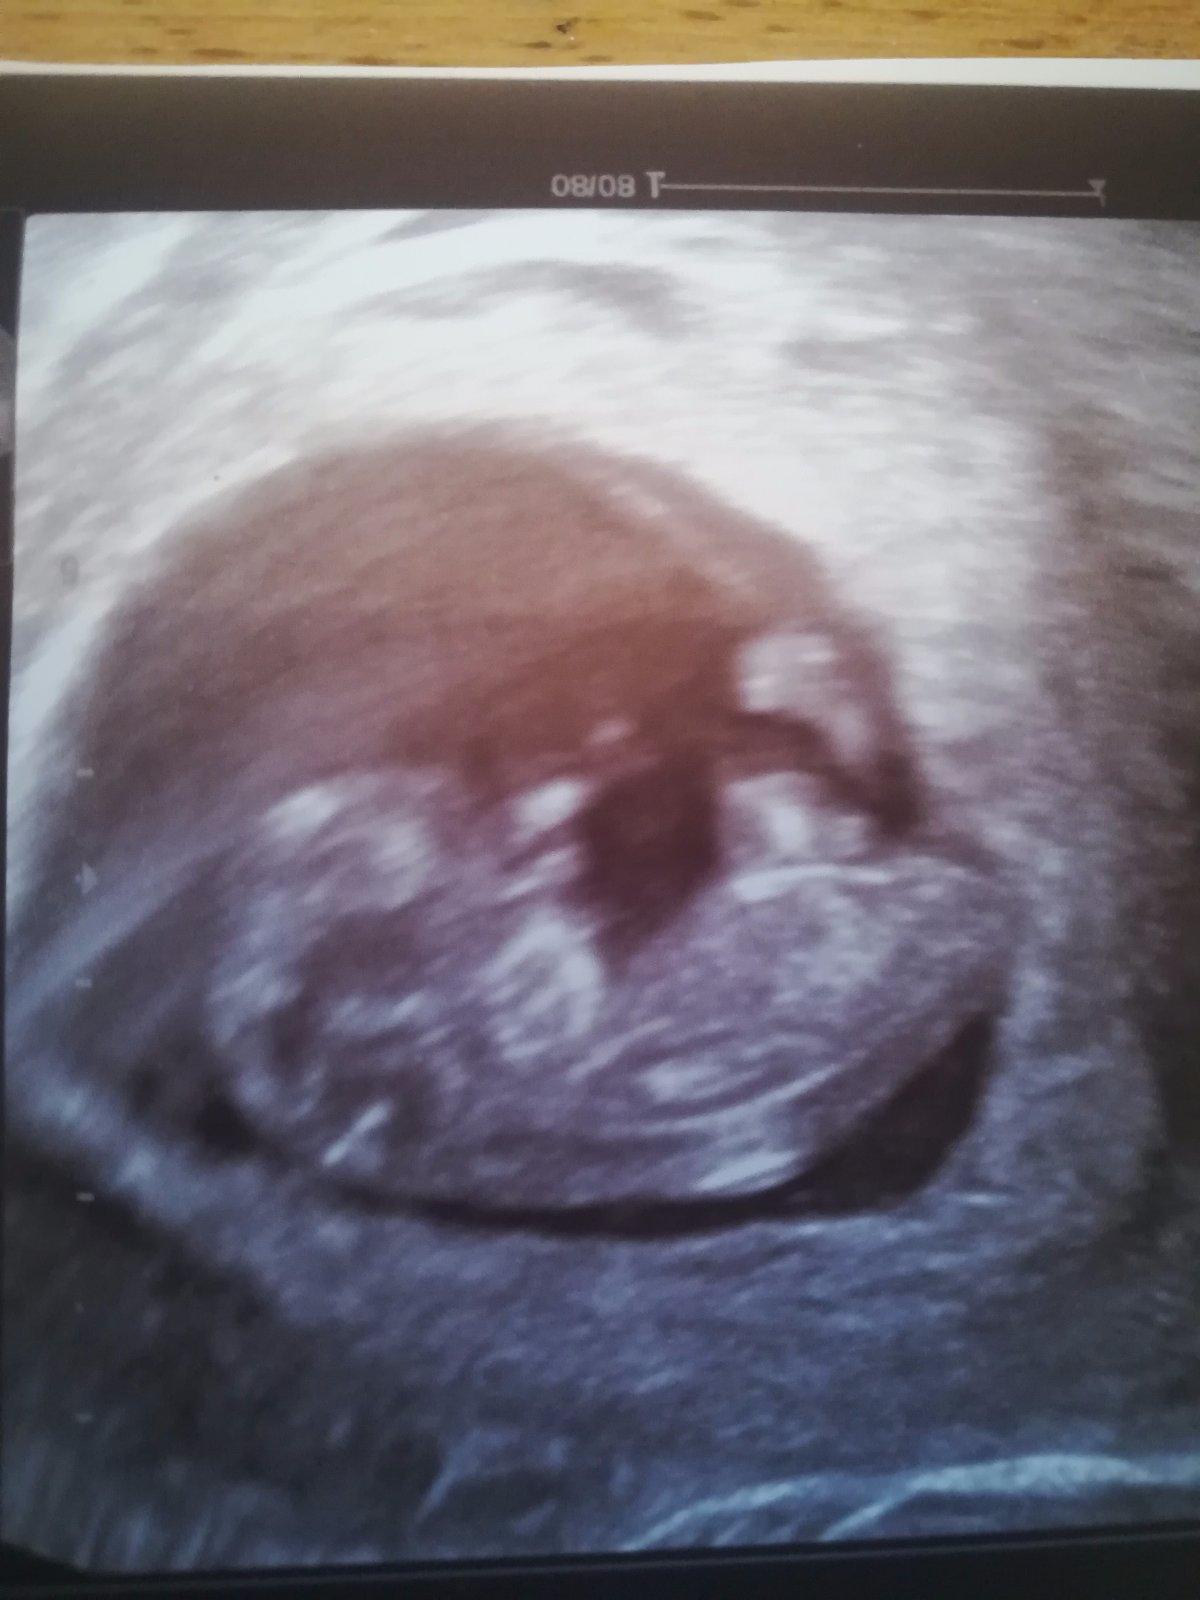

Tak co myslíte holky ? 2 dny do ms